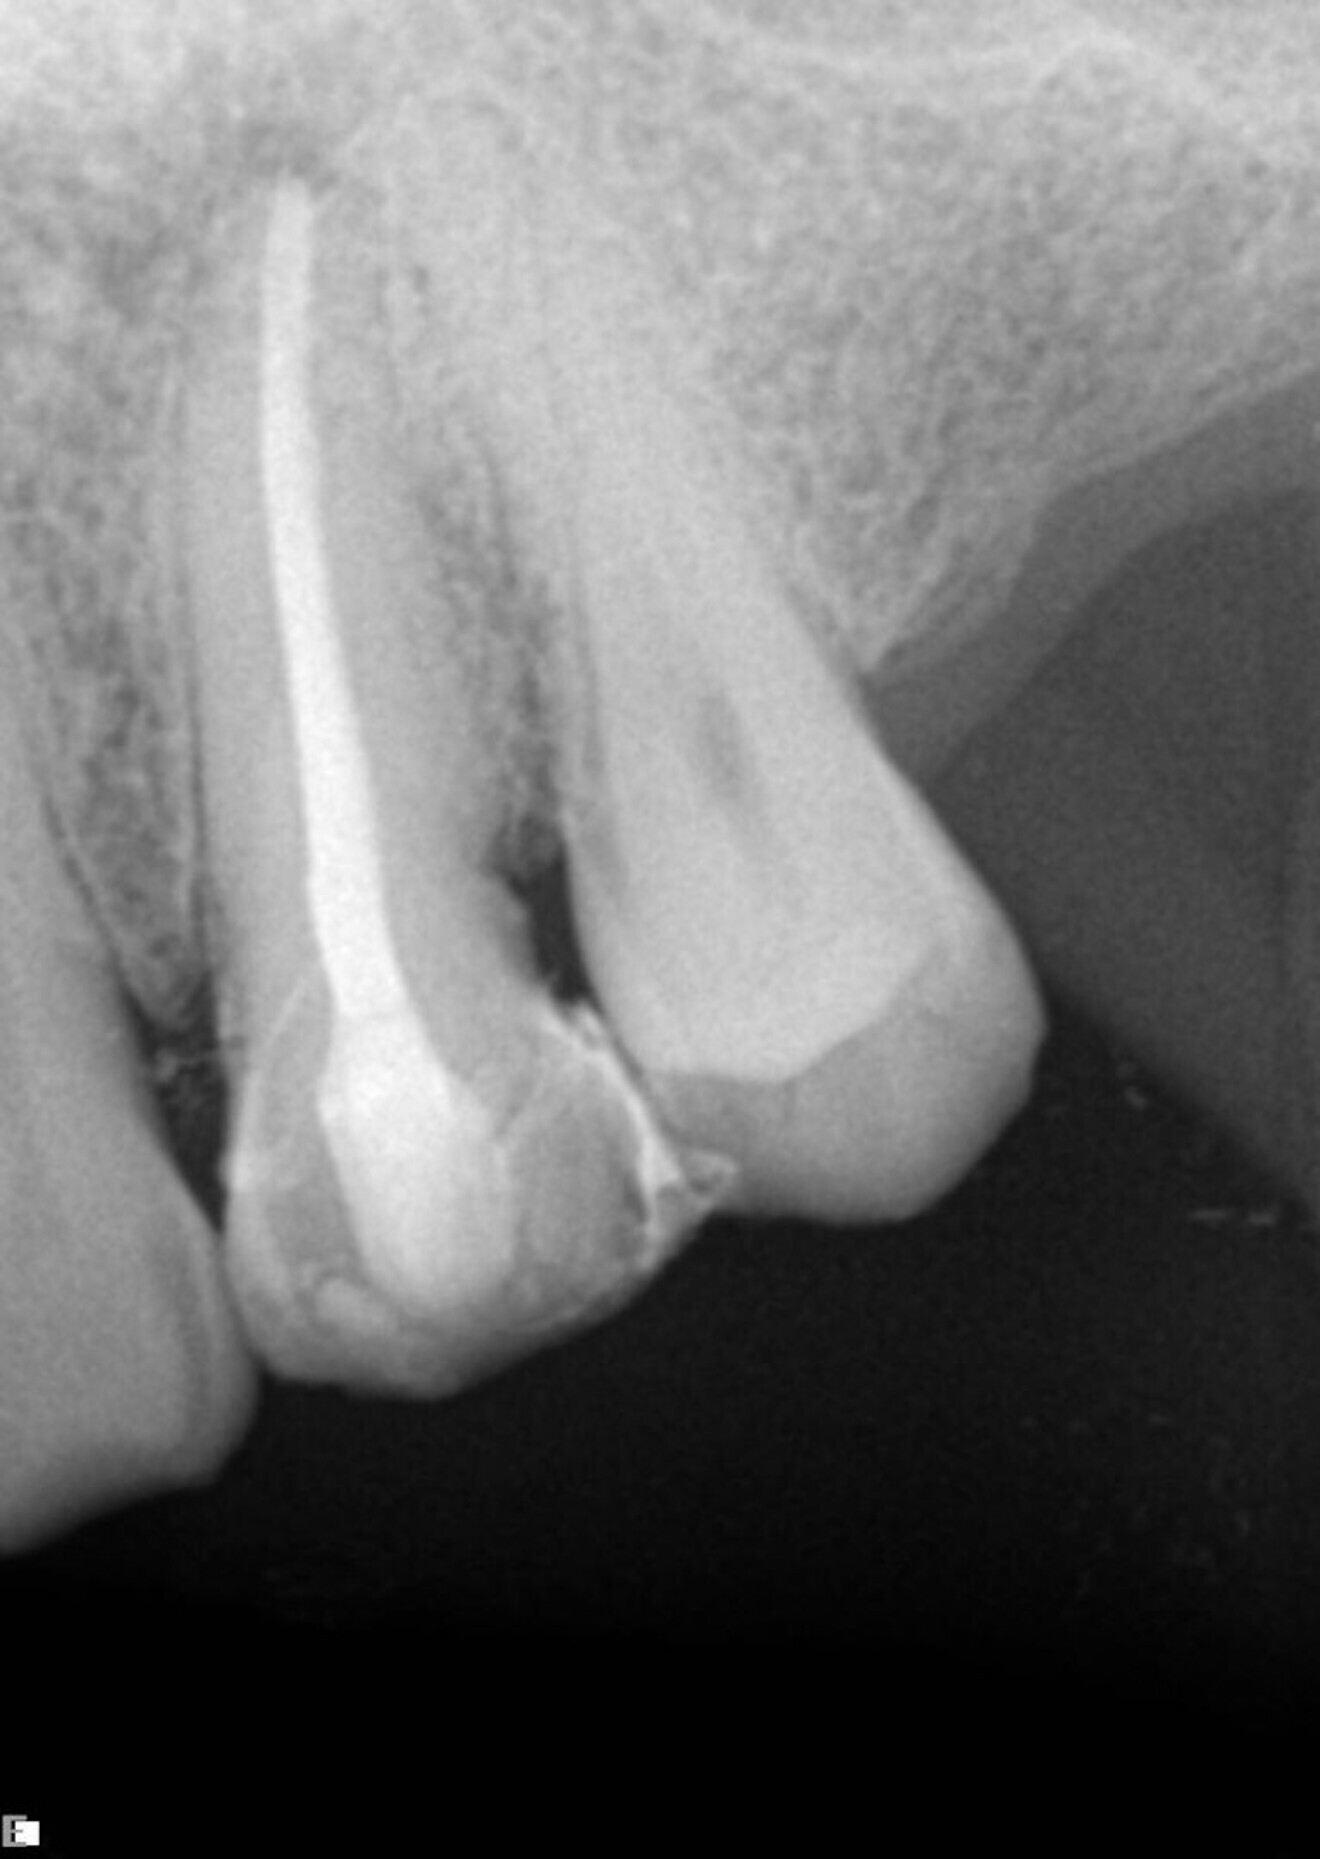

In this first example, the patient was referred for treatment of a sinus tract of the anterior maxilla (Fig. 1). A gutta-percha cone was placed inside the fistula, showing the way to the infection site. This was a straightforward case, prepared using the 25/0.08 Traverse file in the upper part, followed by a 10 K-File (Kerr) to determine the working length and then a 40/0.06 Traverse file taken to working length. Naturally, treatment involved complete chemical preparation and 3D sealing of the root canal space (Fig. 2).

Fig. 1

Fig. 2